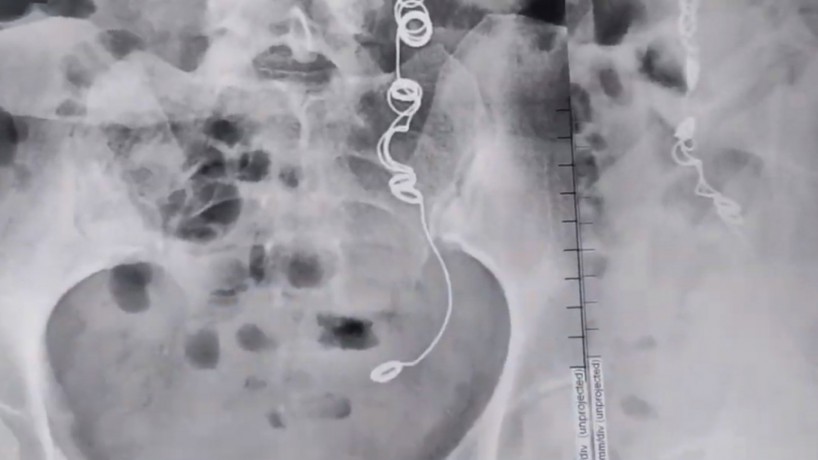

Veja foto do raio-x de mulher que descobrir agulha e linha preso dentro do próprio corpo

Colombiana que fez cirurgia em 2012 e conviveu mais de 10 anos com fortes dores no corpo descobriu uma agulha envolta de linha dentro de seu corpo

Colombiana que fez cirurgia em 2012 e conviveu mais de 10 anos com fortes dores no corpo descobriu uma agulha envolta de linha dentro de seu corpo (Foto: Reprodução/Youtube)